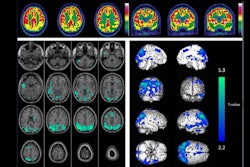

According to the analysis, beta-amyloid levels on PET were elevated in individuals with a history of memory impairment in both parents (n = 455) and in those with only maternal history (n = 1,772) compared with those with only paternal history (n = 632) or no family history (n = 1,554).

Moreover, a paternal history of early-onset memory impairment (age < 65) but not late-onset was associated with elevated beta amyloid on PET compared with individuals with no paternal history, whereas a maternal history was associated with elevated beta amyloid in both early-onset and late-onset groups.

“Maternal history (at any age) and paternal history of early-onset memory impairment were associated with beta-amyloid burden among asymptomatic older individuals,” the group wrote.